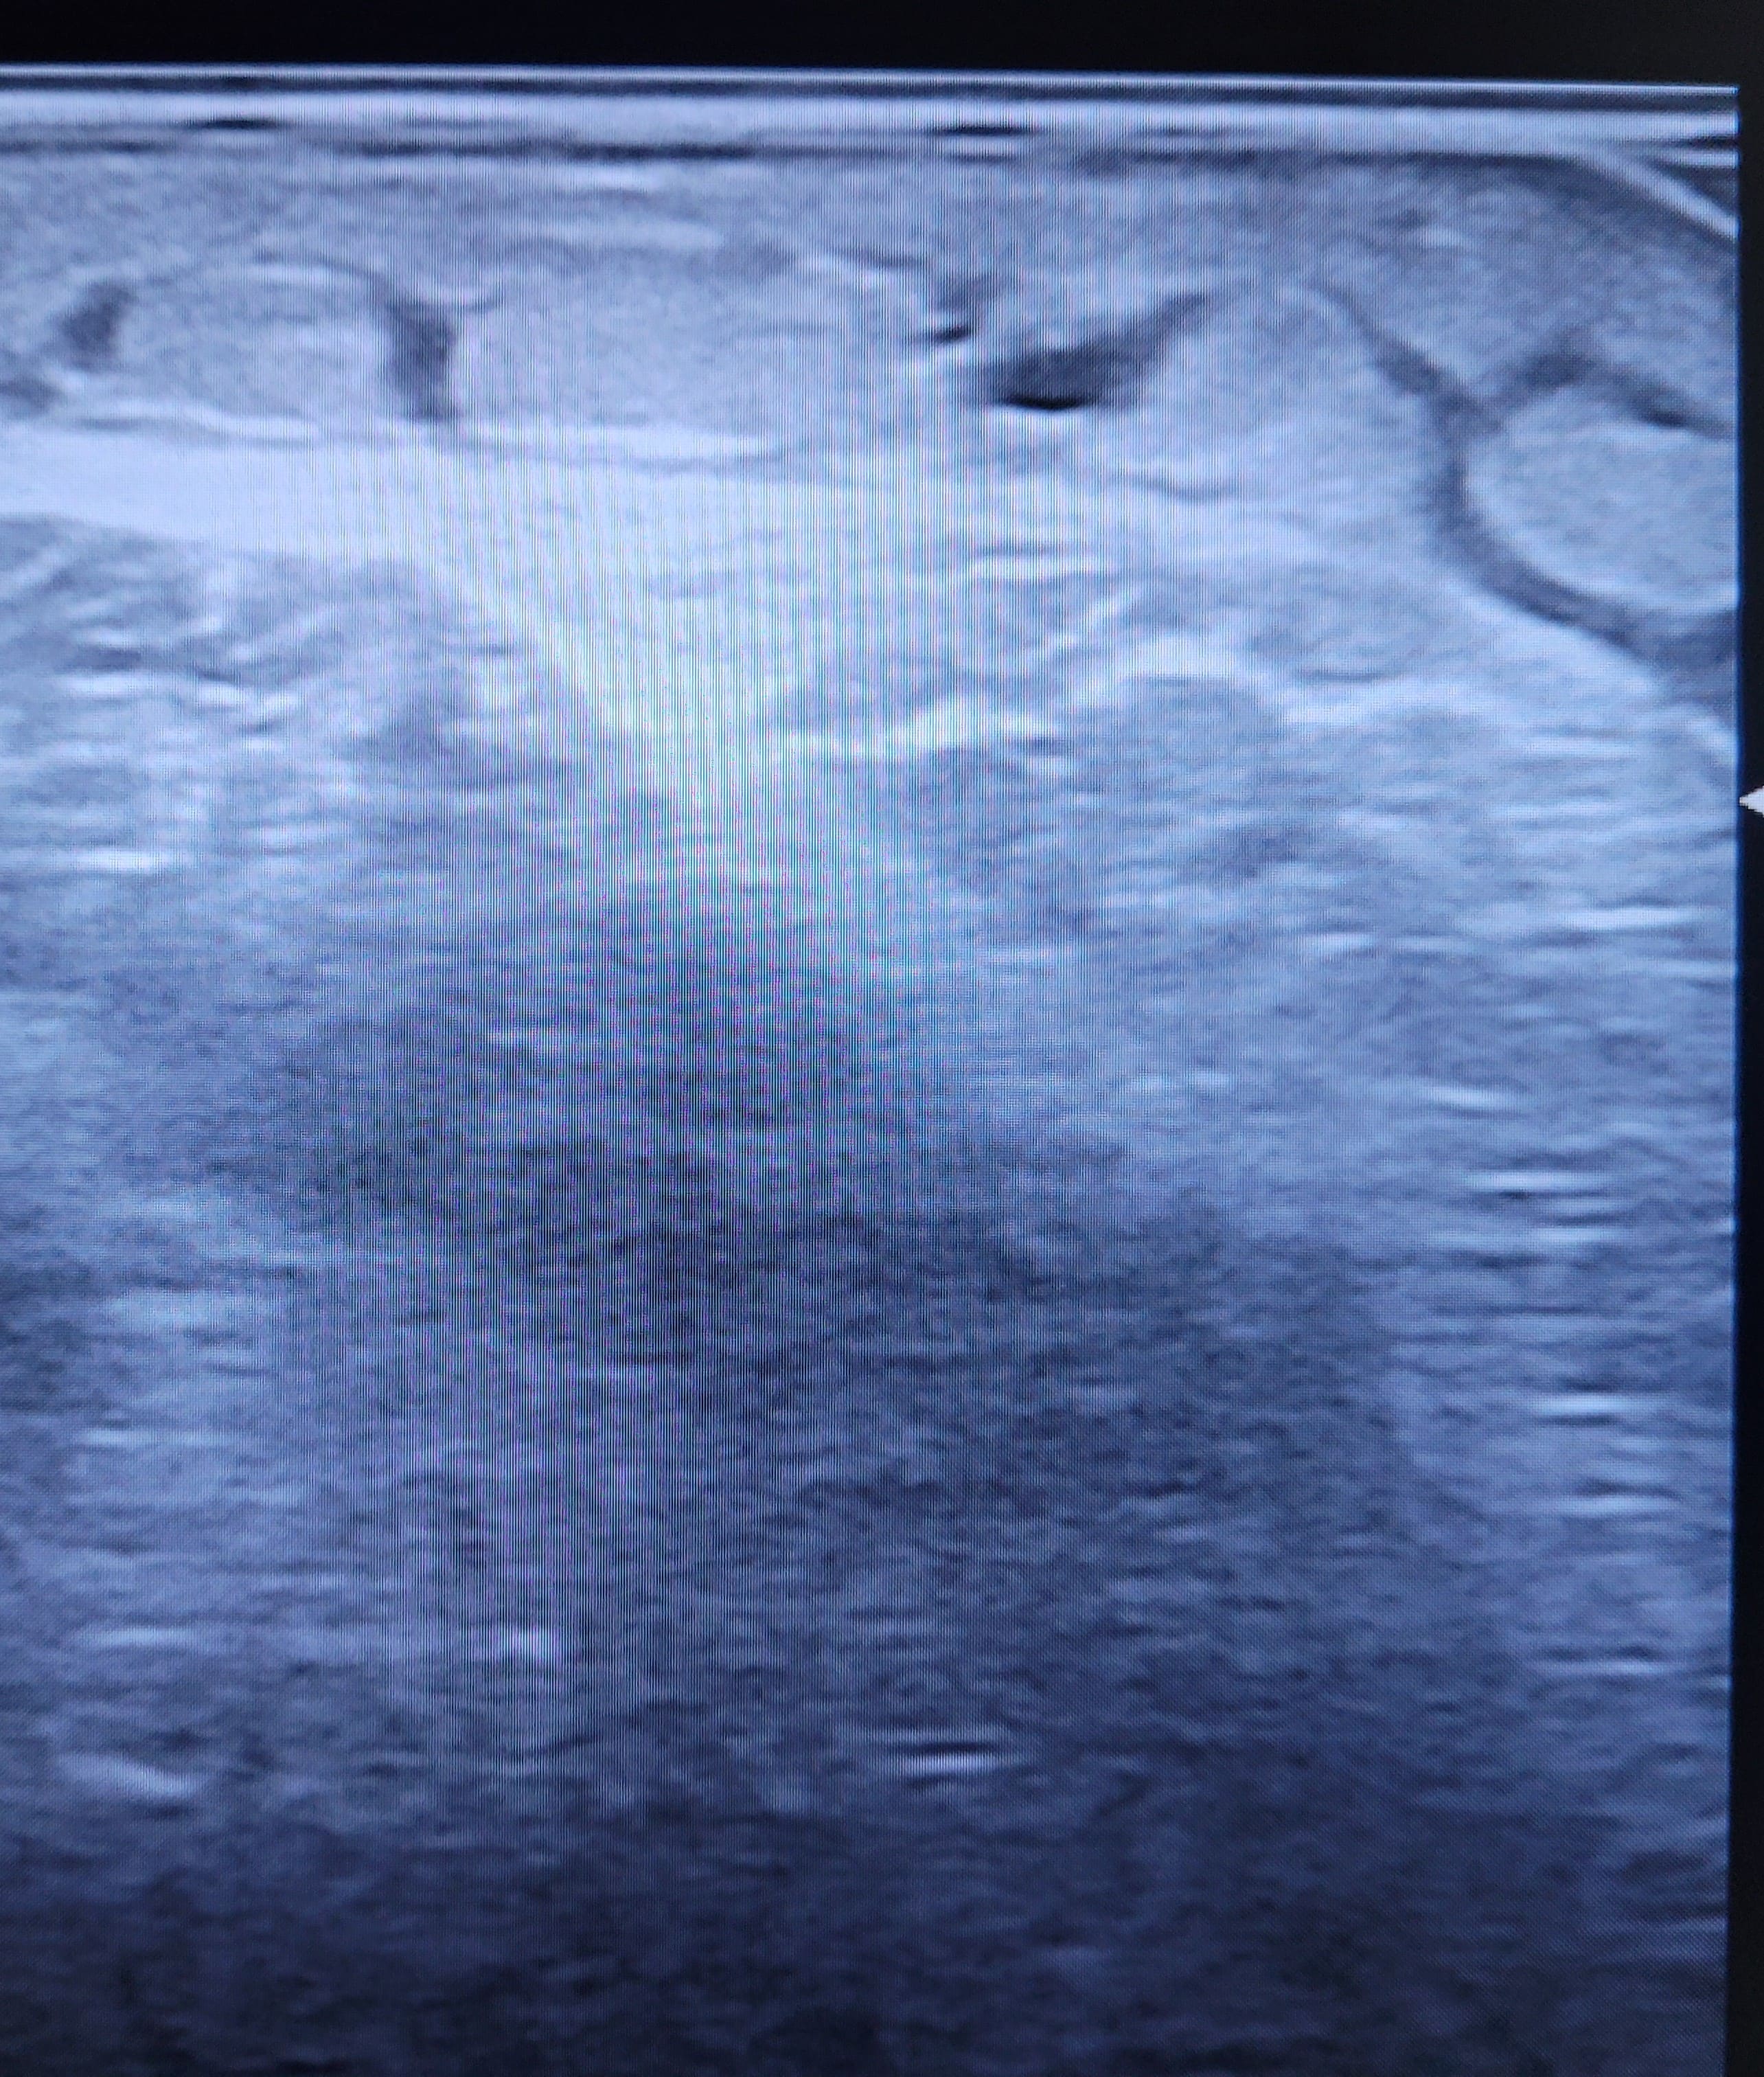

Se realiza una ecografía cutánea: se observan imágenes de “patrón en empedrado o adoquinado”, sugestivo de posible celulitis.